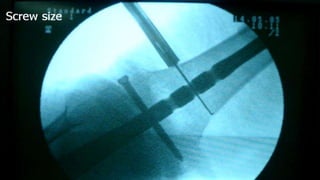

Distal Femur retrograde nailing

Brief steps of distal femoral retrograde nailing of femur